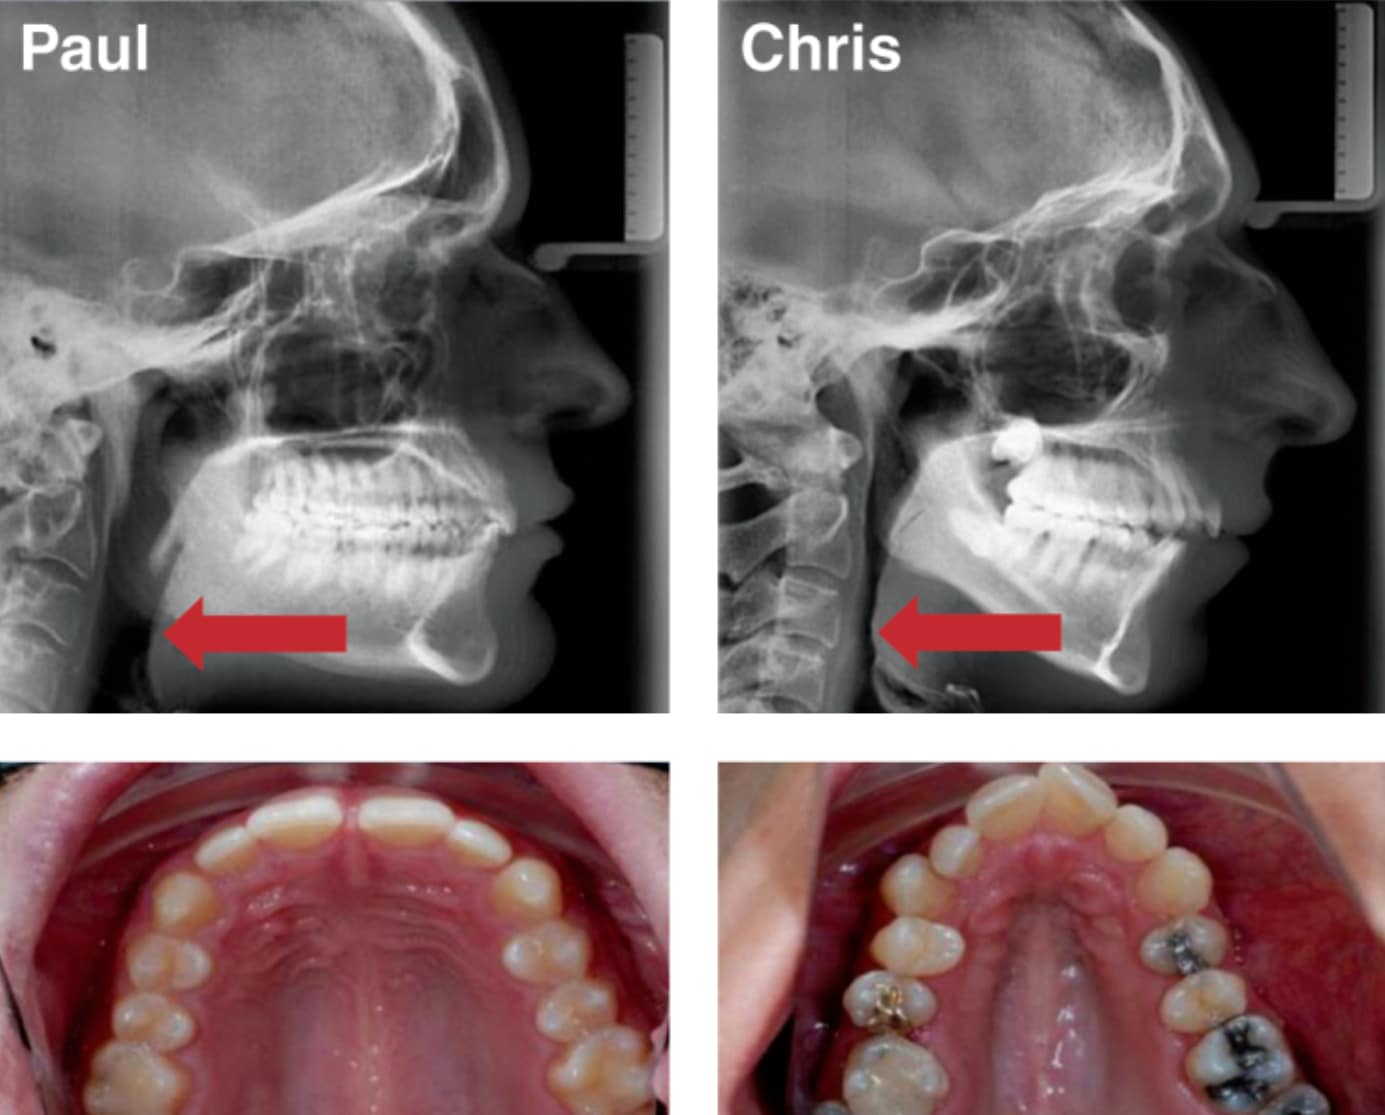

In this example, you can clearly see that with a wide jaw, aligned teeth, there is more room for the tongue.